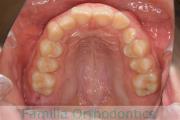

- ≫治療前

上顎

下顎

- ≫治療後

前歯を下げて口元をひっこめたいということで来院されました。かなり強い上顎前突(出っ歯)で、アンカースクリューとマルチブラケット法を用いて上下左右から小臼歯を抜歯して治療を行いました。3年半、40回程度の通院をしていただきました。

かみ合わせが深いため、前歯の圧下(歯ぐきに押し戻す動き)が必要なため、歯根吸収のリスクが高いケースでした。